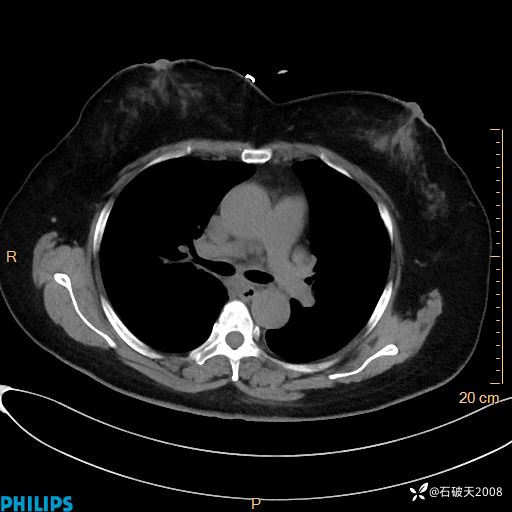

肺结节病?纵膈型肺癌?淋巴瘤?有点意思,欢迎围观

女 52岁 主 诉:咳嗽10余天,咳痰2天。

现病史:10余天前无明显诱因出现咳嗽,呈阵发性干咳,伴咽喉部发痒,无咽痛,无咳痰,无鼻塞、流涕、打喷嚏,无发热、畏寒、寒颤,无头痛、头晕,无胸闷、胸痛,无反酸、烧心,无腹痛、腹泻,无尿频、尿急,无皮疹等,在当地诊所求治,给予口服药物治疗(具体不详),病情无好转。遂在当地社区卫生服务中心开具口服药物治疗(具体不详),疗效欠佳。2天前出现咳痰,在我院门诊求治,行胸部CT提示肺部感染,建议住院,患者要求口服药物治疗,目前仍咳嗽、咳白色粘痰,白天量多,夜间自觉喉部喘鸣音,遂再次来院就诊,以“肺部感染”为诊断收入院。发病以来,神志清,精神可,饮食可,夜间睡眠差,大小便正常,近期体重无明显变化。

动脉期